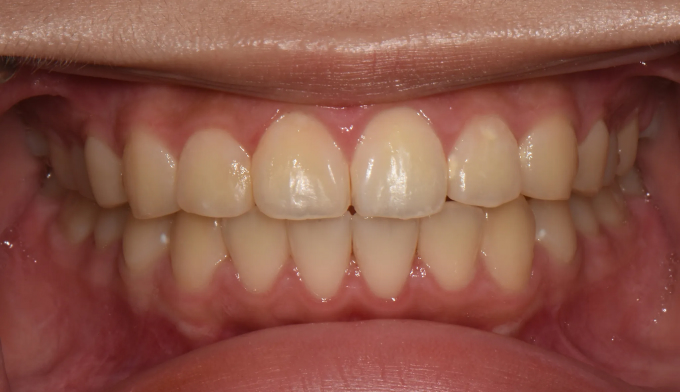

앞니불규칙

Before

After